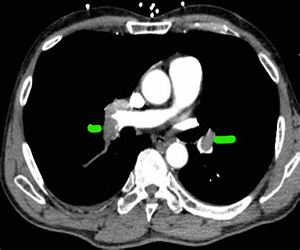

- CT pulmonary angiogram (also called a CT-PA) – Usually diagnostic